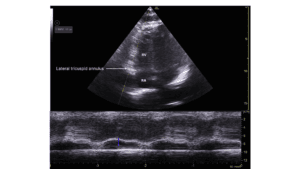

A transthoracic echo (TTE) was ordered for the morning following admission, and a bedside echocardiogram was conducted with a hand-held ultrasound unit (VScan, GE), revealing a dilated hypokinetic right ventricle and grossly normal left ventricular systolic function. The point-of-care cardiac ultrasound (POCUS) led to a new Differential: PE and ACS/right ventricular infarct.

Following the POCUS and confirmatory limited TTE, the patient was sent for an urgent computed tomography (CTPA) to confirm pulmonary embolism, and was admitted to the internal medicine unit. An Urgent full TTE was ordered that evening to document RV dysfunction Respirology was consulted to consider the need for thrombolytics.